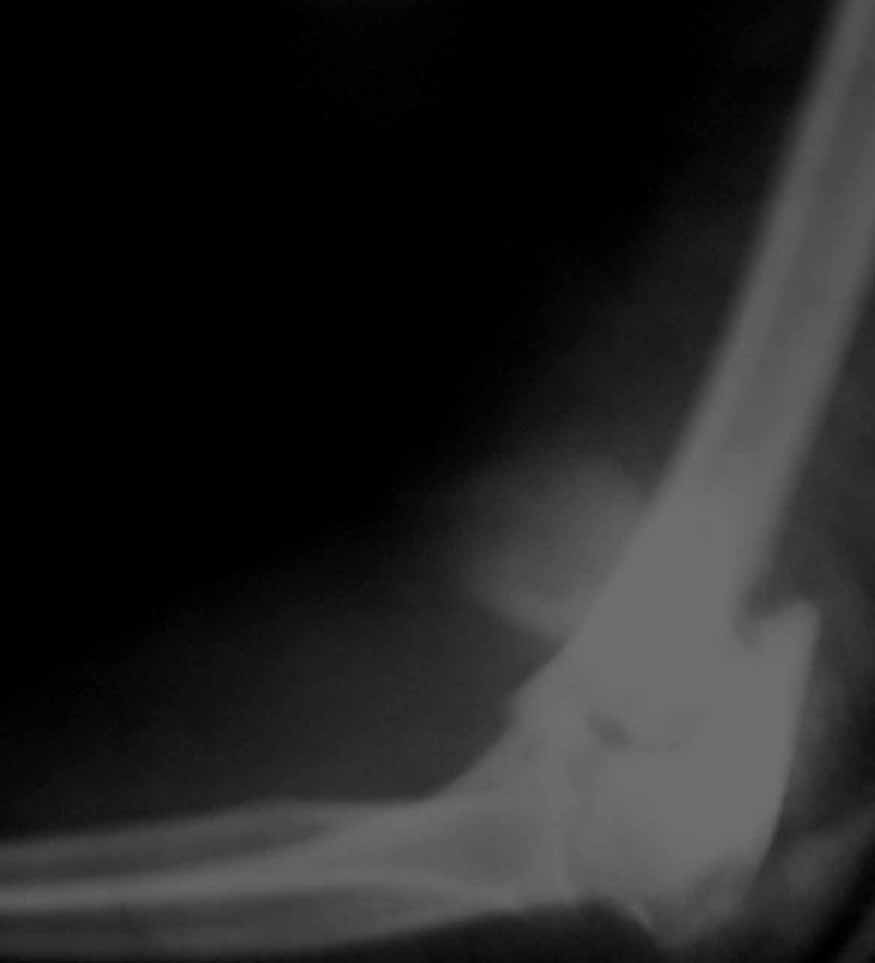

Женщина 42 лет, операция через неделю после перелома.

Д-з - открытый перелом мыщелков со смещзением и локтевой кости

без смещения - падение с лошади.

Остеосинтез закрытый (если так можно выразиться), т.е. без

разрезов. Длительность операции - около 1,5 часа со студентом.